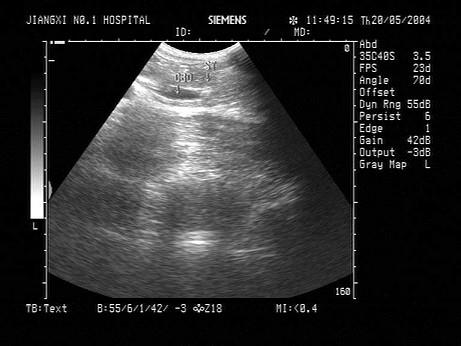

问题 男,27岁,上腹疼痛。声像图如图所示。结合超声声像图,诊断为?(?)

选项 A.胆总管下段结石 B.胆总管下段蛔虫 C.胆总管下段癌 D.胆总下段胆汁淤积 E.胰腺癌

答案 A